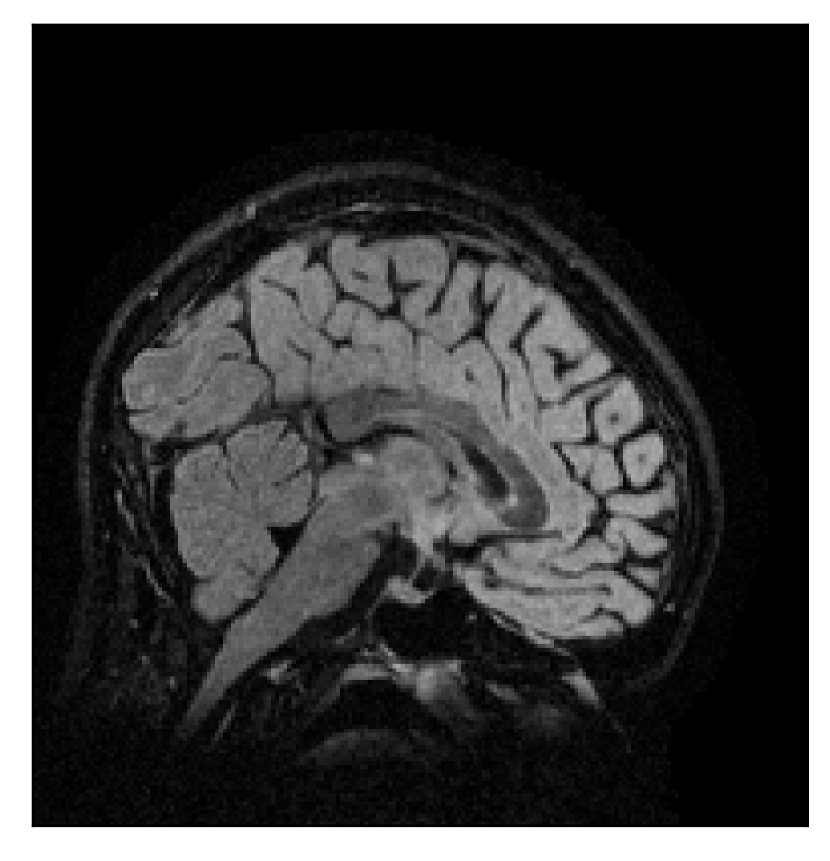

4.1 Experiment 1: robustness test

We gather the results for the robustness test described in Section 3.1 (volunteer 1) in Figures 2, 4, and 6 for motion corruption mechanisms associated to one, two, and five changes of position, respectively. Furthermore, we juxtapose the corrected images with varying degrees of corruption in Figure 8. We observe that the proposed method consistently ameliorates the corrupted scan. The quality indexes based on PSNR and SSIM show only a modest decrease in correction quality as a function of motion complexity (Figure 8).

The motion-corrected full-volume scans were analyzed by a neuroradiologist with 16 years of experience. These were generally deemed of good radiological quality. The motion-related artifacts have been completely removed, and the results are quite close to the ground truth. In Table 3, we organized a more detailed qualitative analysis of the 3D results, geared toward a radiological assessment of the corrected scans.

| Experiment | Contrast | Motion resolution | Blurring | Artifacts | Additional comments |

| Section 3.1, Figure 2 | T2-FLAIR | Completely corrected | Some blurring | No additional artifacts | Good grey white matter differentiation |

| Section 3.1, Figure 4 | T2-FLAIR | Completely corrected | Some blurring | No additional artifacts | Good grey white matter differentiation |

| Section 3.1, Figure 6 | T2-FLAIR | Completely corrected | Some blurring | Darker areas within the white matter | Good grey white matter differentiation |